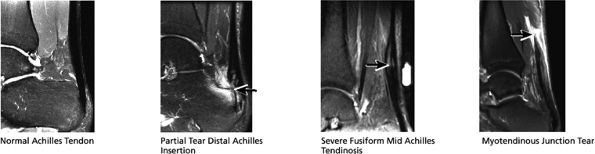

The posterior tendons (the Achilles and plantaris tendons)

FIGURE 5.37 Achilles Tendon.

-

Tendinitis or tendinopathy represents intrasubstance tendon degeneration.

Achilles tendinitis is subdivided into non-insertional tendinosis and insertional tendinitis.

The Achilles tendon has no synovial sheath but is associated with a paratenon or connective tissue envelope.

MR identifies nodular or convex tendon thickening and intratendinous mucoid degeneration.

Haglund's deformity represents insertional tendinitis with a posterosuperior calcaneal bony prominence and retrocalcaneal tendo Achilles bursitis.

In tendinosis or tendinopathy, there is intrinsic or intrasubstance degeneration of the Achilles tendon.

Tendinitis represents the clinical symptoms that develop in association with the degenerative process of tendinosis.

In paratendinitis (also known as peritendinitis, since it refers to the peritendinous tissues), there is generalized inflammation of the tissues surrounding the Achilles tendon (pre-Achilles fat).32

In paratendinitis (peritendinitis) (Fig. 5.106) with tendinosis, there is inflammation of the surrounding tissues with associated tendon degeneration.

The paratenon (also referred to as the peritenon) represents the connective tissue envelope surrounding the Achilles tendon.

Paratenonitis is an inflammation of the Achilles tendon connective tissue envelope (usually limited to the posterior paratenon on MR images).

An irregular pre-Achilles fat pad may be seen with paratendinitis (peritendinitis) with or without abnormal Achilles tendon morphology.

Achilles tendon rupture usually occurs 2 to 6 cm proximal to its os calcis insertion.

Sagittal images are used to identify the proximal and distal tendon ends.

Axial FS PD FSE images are used to confirm complete rupture (an intact plantaris may simulate an intact tendon in the sagittal plane).